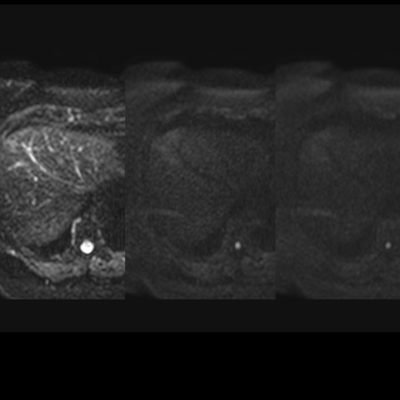

El estudio se complemento con resonancia magnética, donde se demostró la presencia de múltiples imágenes focales hepáticas confluentes con disminución de la señal en secuencias fuera de fase, no mostrando alteración de la señal en secuencias potenciadas en T2, sin signos de restricción al pulso difusión ni refuerzos anómalos luego de la administración de contraste endovenoso, estos hallazgos confirman la sospecha de esteatosis focal multinodular (fig. 5, 6 y 7).

En estos casos se recomienda realizar RM para confirmar la presencia de grasa en las “lesiones” identificadas y descartar otras etiologías, demostrando disminución de la señal en secuencias fuera de fase, sin alteración del pulso difusión (fig. 12 y 13).